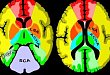

2017.10.08神经科必备:最全脑血管供血区图谱

双节福利,快收藏吧!